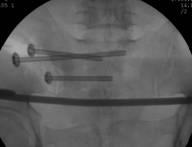

术中C臂

整个手术1小时内完成,通过术后CT影像证实3D打印导航模板引导骶髂螺钉置入安全、准确、创伤较小,手术时间短,患者也很快得到了较好的恢复。